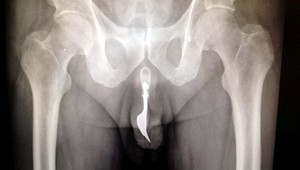

ČADCA / Pani Jesenská mala začiatkom februára obrovský strach o svojho manžela. Ten po dávnejšej operácii srdca, dostal vysoké horúčky a tak mu zavolala záchranku. Z prístupu však bola vtedy rodina zhrozená. Postup poskytnutia zdravotnej starostlivosti nakoniec prešetrovala nielen nemocnica v Čadci.

Vo februári dostal Ľudovít vysoké teploty. Nevedela si s nimi poradiť ani jeho manželka, ktorá je zdravotná sestra. Keď zavolala na linku 112, odporučili jej studené zábaly. Tie však svojmu manželovi, ktorý prekonal vážnu operáciu srdca, dať nemohla. Tie isté odporúčania dostali aj od privolanej lekárky.

"Pracovníčka, ktorá bola na výjazde, urobila všetko čo mohla v súlade so zákonom," uviedol riaditeľ Martin Šenfeld. "Ja si myslím že lekárka pochybila. Rešpektujem však rozhodnutie nemocnice," hovorí pacient Ľudovít Jesenský. Ľudovítova manželka, teraz pracuje v nemocnici v Čadci ako zdravotná sestra. Pochopiteľne sa o svojho manžela bála. Podnet podali preto, že sa im nepáčil prístup záchranárky a to, že Ľudovíta nevzali do nemocnice. "Nie každý výjazd, musí končiť hospitalizáciou," dodal Šenfeld.